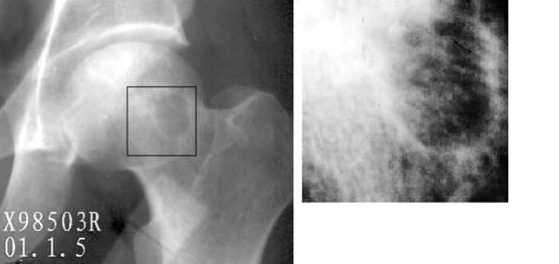

Диагностика ТБС рентгеном и асептический некроз: особенности лечения

Раздел: Снимки-откровения